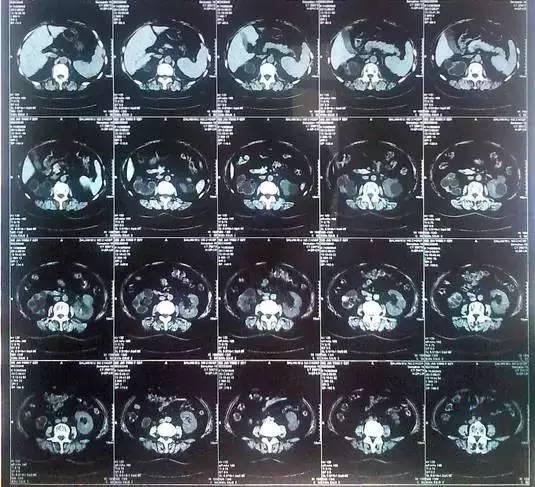

55歲的老何是金華東陽市橫店鎮(zhèn)人,一名普通工人。因為頻繁腰疼去醫(yī)院檢查,結(jié)果CT顯示,他的左腎里竟然密密麻麻布滿了石頭,幾乎把整個腎都塞滿了,手術(shù)從左腎取出了420顆結(jié)石!

醫(yī)生看了CT的結(jié)果顯示,非常嚴肅的告訴他,他的左腎已經(jīng)被結(jié)石占滿,必須馬上手術(shù)治療。這次手術(shù)讓主刀醫(yī)生觸目驚心,他們居然從老何的左腎取出了420顆結(jié)石。這是他們手術(shù)生涯上從來沒有遇到過的病例。